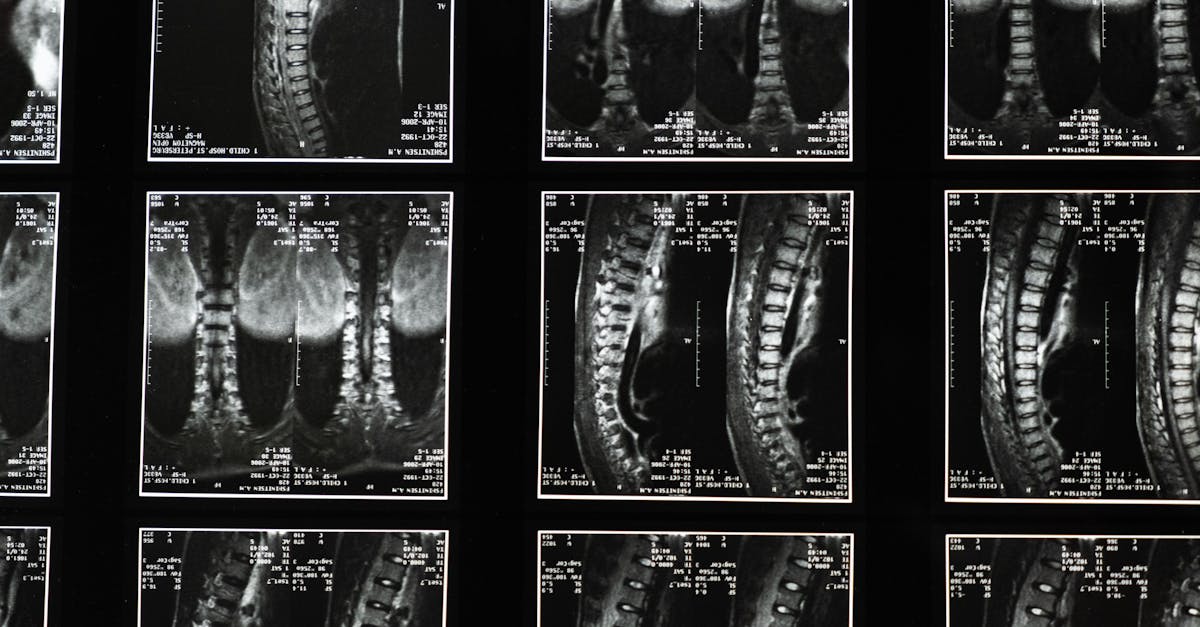

Comment la décompression neurovertébrale aide à prévenir l’aggravation d’un pincement discal

EN BREF La décompression neurovertébrale est un traitement efficace pour prévenir l’aggravation d’un pincement discal. En appliquant une force de traction sur la colonne vertébrale, cette […]

Comment la décompression neurovertébrale aide à prévenir l’aggravation d’un bombement discal

EN BREF La décompression neurovertébrale est une méthode thérapeutique avancée qui aide à traiter le bombement discal en soulageant la pression sur les disques vertébraux. Cette […]